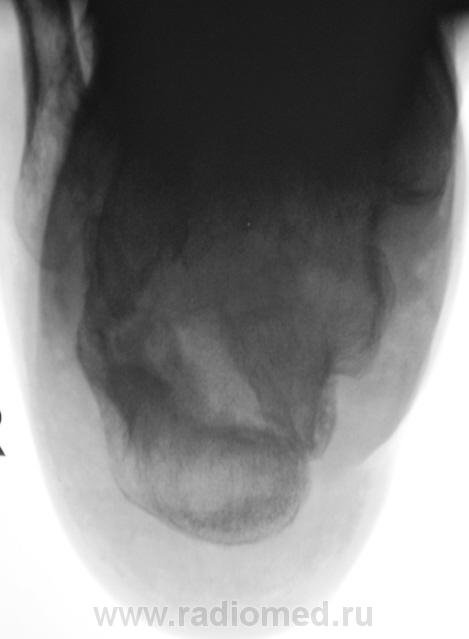

Лечение состояло из "множества рентгенов" и гипса. Срок - 5 месяцев.

Сейчас думают об остеомиелите.

Контуры пяточной кости относительно четкие, разрежение структуры пяточного бугра, в проекции перелома уплотнение структуры кости( имею в виду последние снимки).Клиника остеомиелита есть?

Клиники остеомиелита, с моей точки зрения, нет.

А что Вы в протоколе написали?Я тоже не вижу остеомиелита.

Во-первых, деформация пяточной кости; во-вторых, отсутствие консолидации, через некоторое время и ложный сустав сформируется. Неоднородное уплотнение костной структуры в теле кости может быть обусловдено как остеомиелитом, так и перераспределением нагрузки.

Признаков остеомиелита не вижу, только консолидир перелом с неуд стоянием отломков.